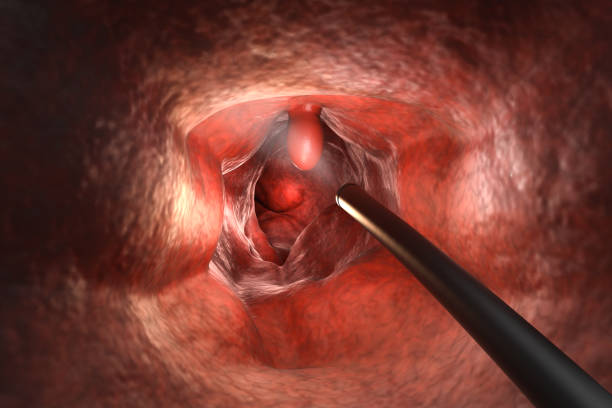

장폐색으로 인한 변비는 대장 내부에서 대변이 막혀서 대변을 배출하기 어려운 상황을 말합니다. 대변이 막혀 있어서 배출이 어렵고, 배출하려고 노력하면 통증이나 출혈 등의 증상이 나타날 수 있습니다. 대장 내부에서 대변이 막히는 원인으로는 대장암, 섬유화, 협착, 분절증 등이 있을 수 있습니다.

- 수술: 치료가 어려운 경우나 합병증이 있는 경우 등에는 수술적 치료가 필요합니다. 부위에 따라 다양한 수술 방법이 있습니다.